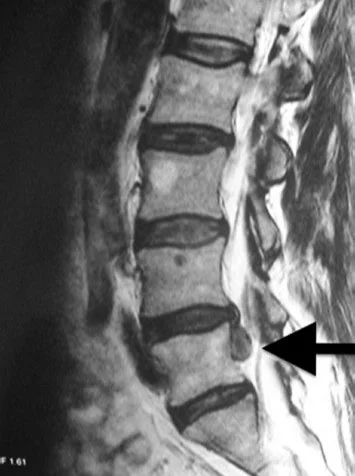

Let’s use the case of someone who herniated a lumbar disc for sake of example to explain how this approach can be defined.